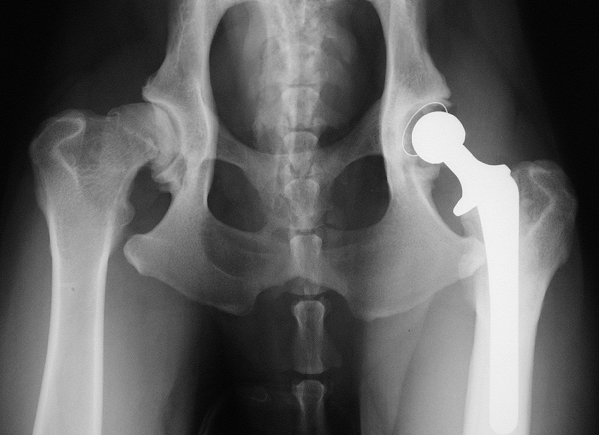

A cemented total hip replacement A cementless total hip replacement

A cementless total hip replacement